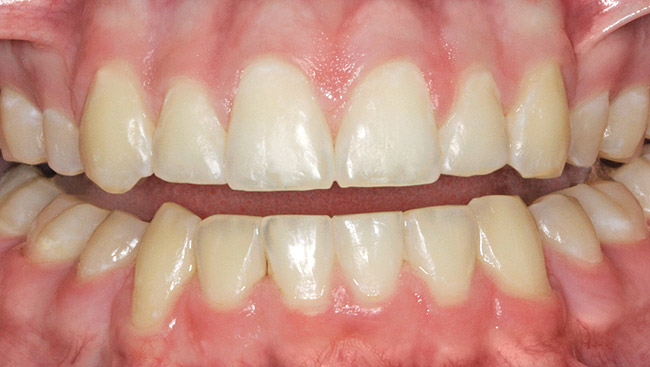

Figure 3  White spot lesions evident after orthodontic therapy (photograph courtesy of S. Paris and H. Meyer-Lueckel).

Figure 3

Figure 4  White spot lesions are imperceptible, blending with natural tooth color, after caries infiltration therapy (photograph courtesy of S. Paris and H. Meyer-Lueckel).

Figure 4